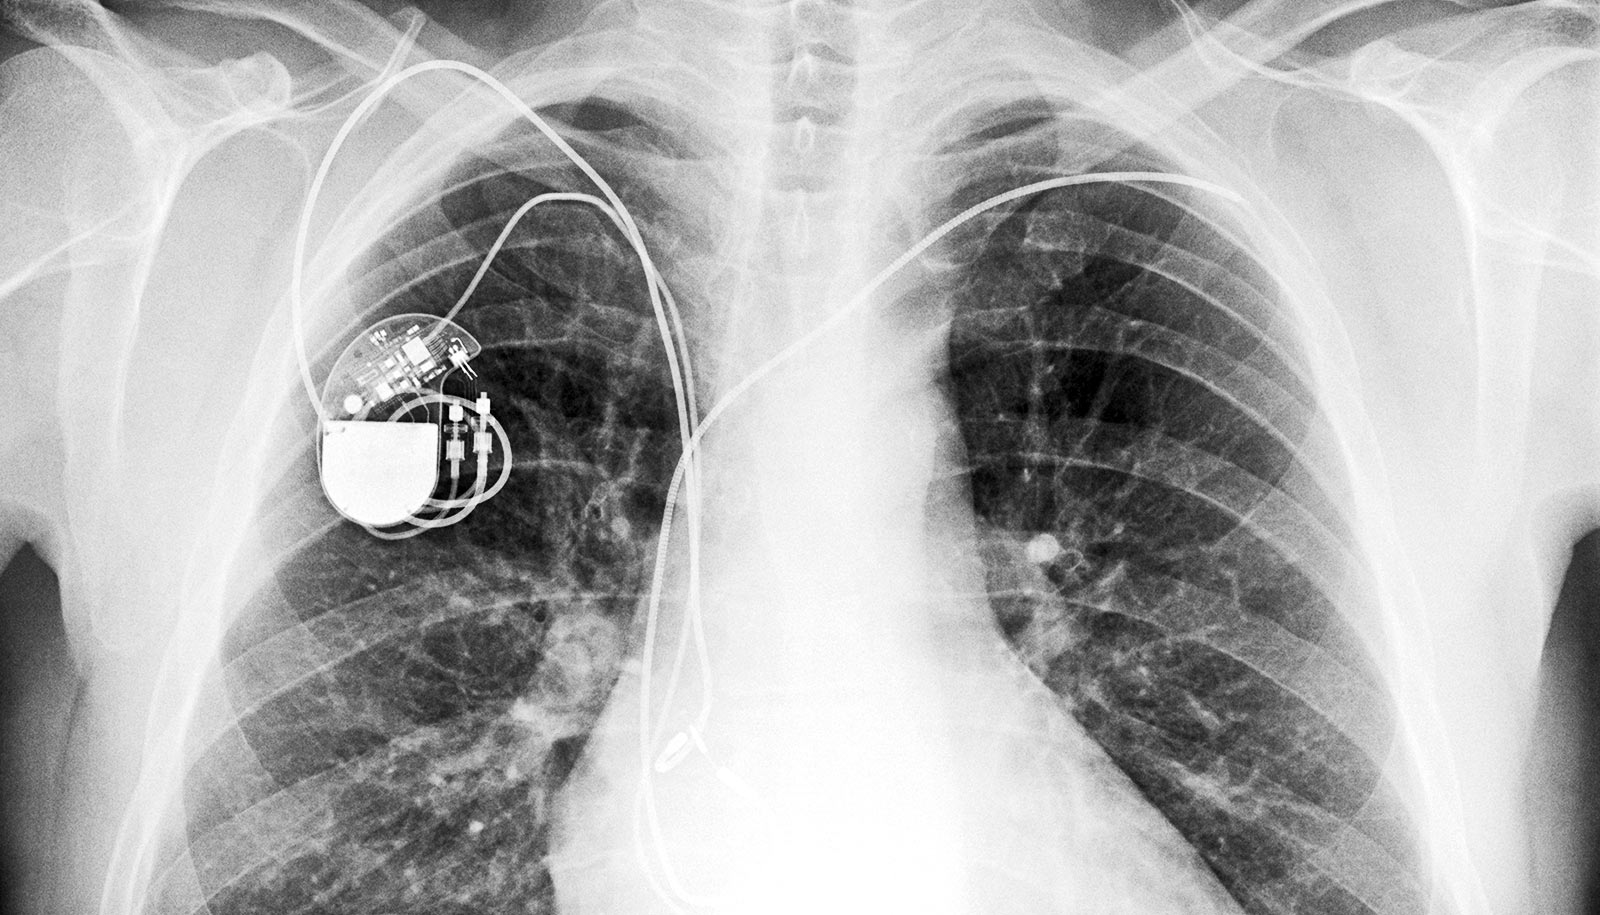

From www.researchgate.net

CXR of dual chamber pacemaker. An anteroposterior and lateral view Electrodessication Pacemaker Pacemaker problems† consider thermal pencil cautery. According to in vitro studies, electrodessication is considered safe in patients with implanted cardiac devices. The electrosurgical unit is a very useful tool widely used in dermatology to treat benign and malignant skin lesions and to achieve hemostasis during. It is safe with electronic equipment, such as pacemakers. While not an absolute contraindication to. Electrodessication Pacemaker.